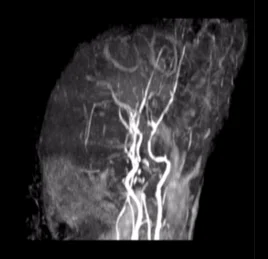

• 뇌혈관 조영술

뇌혈관 이상 (손상/기형)

• MRA- 뇌혈관 조영술